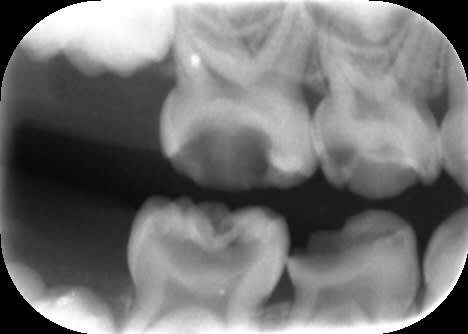

Radios de contrôle.

Pour 65, on voit sur la vue clinique une large canal palatin ovalaire. L'image radiographique correspond probablement à la fusée d'IRM dans l'entrée de ce canal. Je ne pense pas avoir perforé (j'espère !).